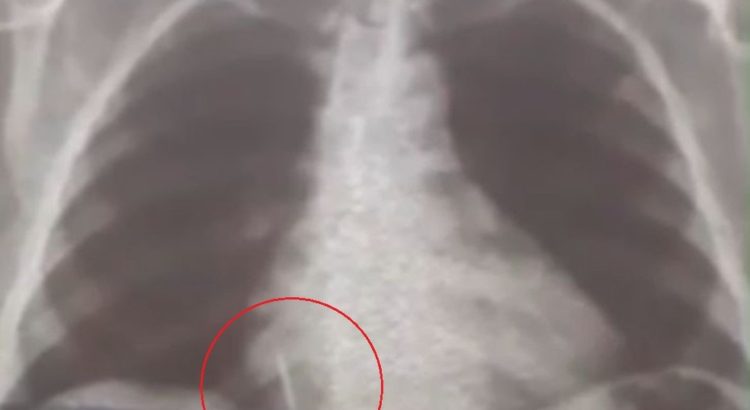

Broca de dentista se solta durante atendimento e vai parar dentro de pulmão de paciente no RN

Foto: Reprodução

Uma paciente de 55 anos engoliu uma broca durante a extração de um dente em uma unidade de saúde no município de Lajes, Região Central potiguar. O caso aconteceu no dia 26 de julho.

Iolanda Mariano de Melo Simplício está com o material alojado no pulmão deste então. O filho dela conta que a mãe sente muitas dores e já perdeu cerca de 10 quilos desde o ocorrido.

“A Secretaria Municipal de Saúde nos deu assistência para a realização dos exames. A gente foi para Natal inúmeras vezes com ela para fazer tomografia, raio-x, hemograma, risco cirúrgico, mas até agora nada. Já são quase 29 dias e praticamente não temos resposta. A gente quer uma solução, porque é um corpo estranho que está dentro do pulmão dela”, conta Rohnhalyson Mariano.

A Prefeitura de Lajes informou que a cirurgia da paciente chegou a ser marcada para 11 de agosto, mas não aconteceu pois um dos equipamentos necessários para o procedimento quebrou.

O município informou que está se preparando para realizar a cirurgia de forma particular. A Prefeitura está analisando os orçamentos e vai pagar pelo procedimento de retirada do objeto do pulmão da paciente.

De acordo com a secretaria municipal de saúde, o dentista responsável pelo acidente foi afastado e não voltará a trabalhar no município, que já providencia um profissional substituto.